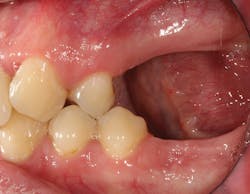

Although unpredictable, a greater amount of alveolar ridge loss following extraction usually occurs in the horizontal dimension and affects the buccal bone of the ridge.3 In fact, 50% of alveolar bone dimension can be lost after tooth extraction, with losses reported of up to 6–7 mm (figure 1). Two-thirds of this loss of bone volume can occur within the first three months of tooth extraction.4

Because of this alveolar resorptive pattern after tooth extraction, bone grafting the extraction socket after tooth extraction procedures has become a solution that attempts to limit the amount of hard- and soft-tissue loss. There are many systematic reviews in the literature that compare the results of residual ridge dimension following tooth extraction after the use of a bone graft (with or without a membrane) versus extraction alone without grafting.7

Indications for bone grafting extraction sites include:

• site development to increase hard and soft tissue for pontic sites in fixed bridge prosthetics (figures 9–14);• correcting bone defects impinging upon anatomical structures after tooth extraction, such as oroantral communication (figure 18); and

• preserving tissue structure for subsequent dental implant therapy.Decision matrix